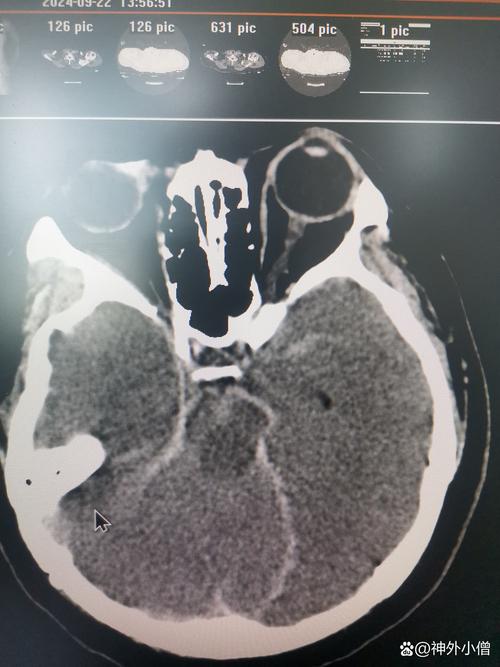

- 脑出血:也叫出血性脑卒中,是因为脑血管破裂,血液流入脑组织,压迫并破坏脑细胞,最常见的原因是高血压导致血管破裂,或血管畸形破裂。

第二部分:房颤如何引起“脑出血”?(这是相对少见但严重的并发症)

“脆弱的血管” + “抗凝药” = 脑出血风险增加:

- 如果一个房颤患者同时患有高血压,他的脑血管本身就比较脆弱。

- 在这种情况下,即使血压出现一过性的急剧升高(如情绪激动、用力排便等),也可能导致这些脆弱的脑血管破裂出血。

- 由于患者正在服用抗凝药,血液无法正常凝固,出血会持续,甚至加重,从而引发脑出血。

【关键点】:房颤本身不直接导致脑出血,而是房颤患者为了预防脑梗而进行的抗凝治疗,在合并高血压等血管病变的基础上,增加了脑出血的风险,对这类患者的血压控制要求极高。